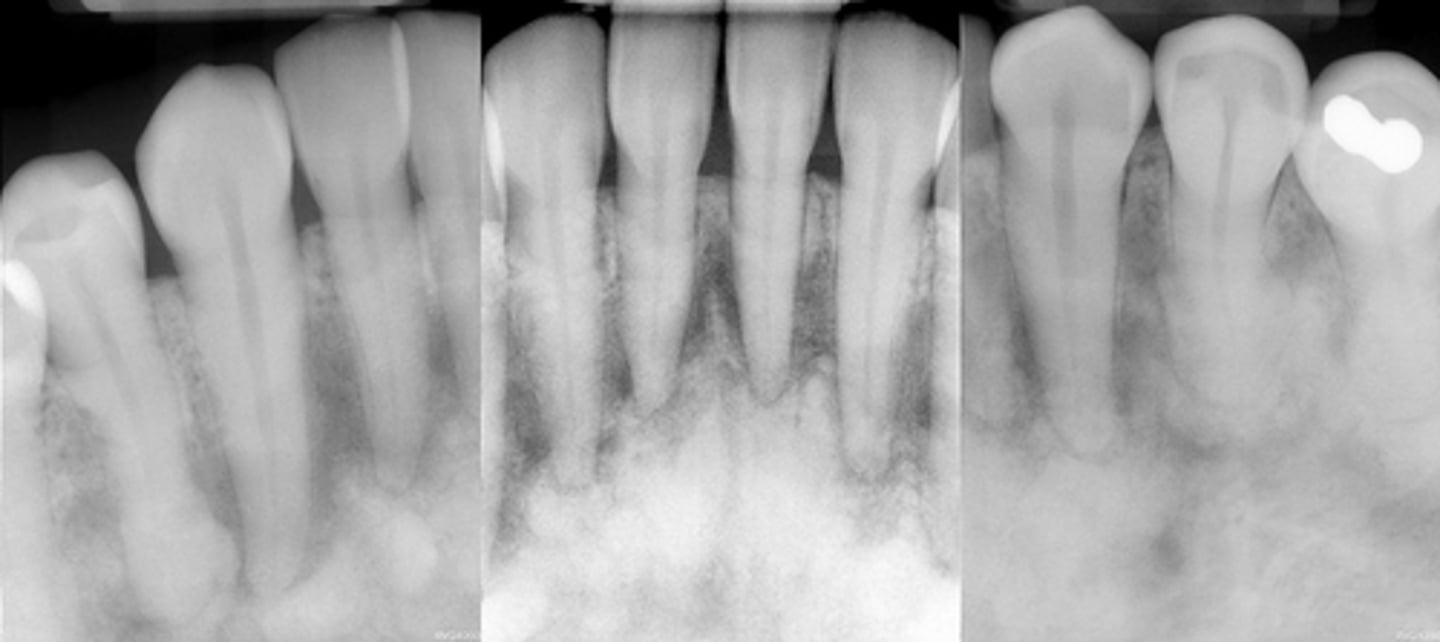

Fibrous dysplasia

Monostotic Fibrous Dysplasia- (a) earlier more radiolucent stage. (b) 18 years later more radiopaque stage

images showing a simple bone cyst developing within a focus of fibrous dysplasia